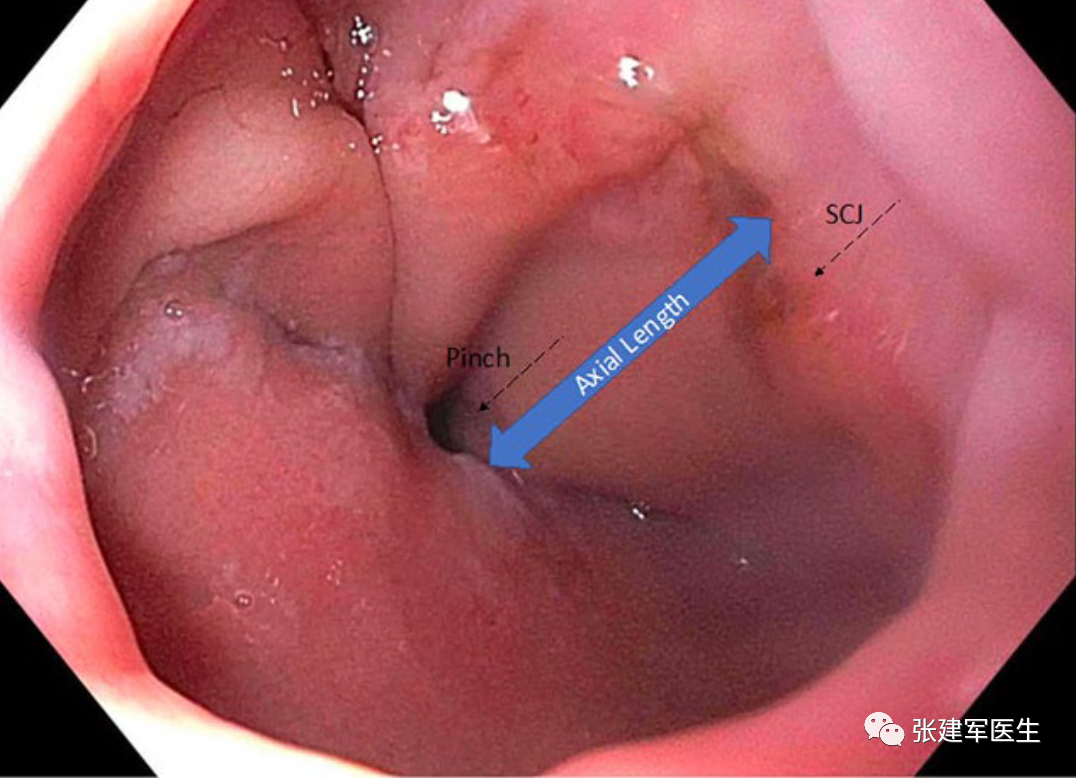

胃十二指肠镜检查

能直观评估食管、胃以及十二指肠粘膜状态,诊断糜烂性食管炎及巴雷特食管(Barrett's esophagus),明确食管裂孔疝的大小及类型,确定食管裂孔疝有无扭转。